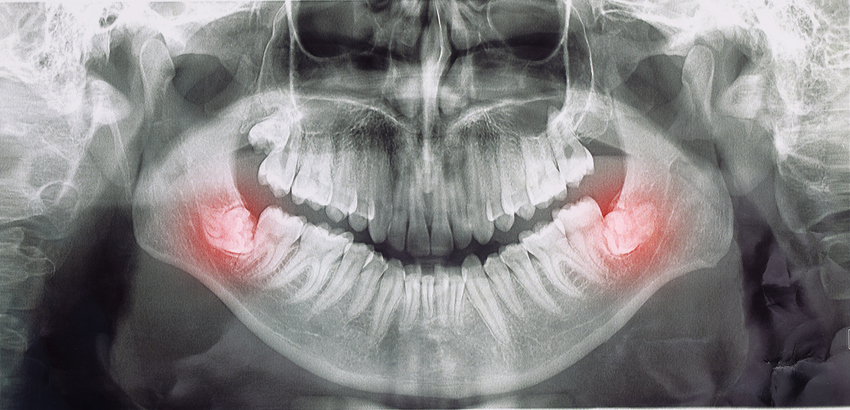

Through imaging, we can often see how a person’s wisdom teeth are developing before they erupt, catching any early signs that issues are likely to arise. The earlier we discover these problems the easier the procedure and recovery process are.

Wisdom teeth are the last teeth to come in, and many people’s mouths aren’t big enough to accommodate them. When a person’s wisdom teeth try to erupt in a crowded environment, you can experience issues ranging from impaction (stuck under the gum), to partial eruption, to eruption at an angle that puts pressure on nearby teeth and creates a difficult area to keep clean. Over time, this can even lead to cavities on the 2nd molars, which if the damage becomes severe enough, could require the 2nd molars to be extracted as well.

For some patients, there are signs that signal they could need an extraction, whether that’s pain, swelling, infection, or discomfort when chewing. For others, pain hasn’t become part of the equation yet, but imaging shows there could be problems down the line if the wisdom teeth continue to develop without intervention. Getting imaging early, and taking preventative measures before your wisdom teeth cause pain or infection is critical to avoiding complications.

- Imaging shows that your wisdom teeth are creating an environment where you are likely to experience issues such as decay, gum disease, or damage to nearby teeth.